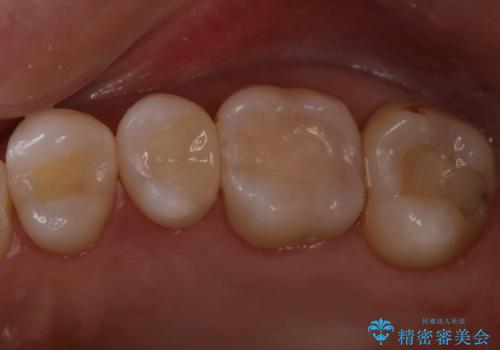

定期検診で虫歯発見。セラミック治療

- 77,000円費用は治療当時の料金となります

まずは虫歯をしっかりと取る事が大切です。

虫歯をとった後は、削った形に型を取る事で隙間なく歯にあった被せ物ができてきます。